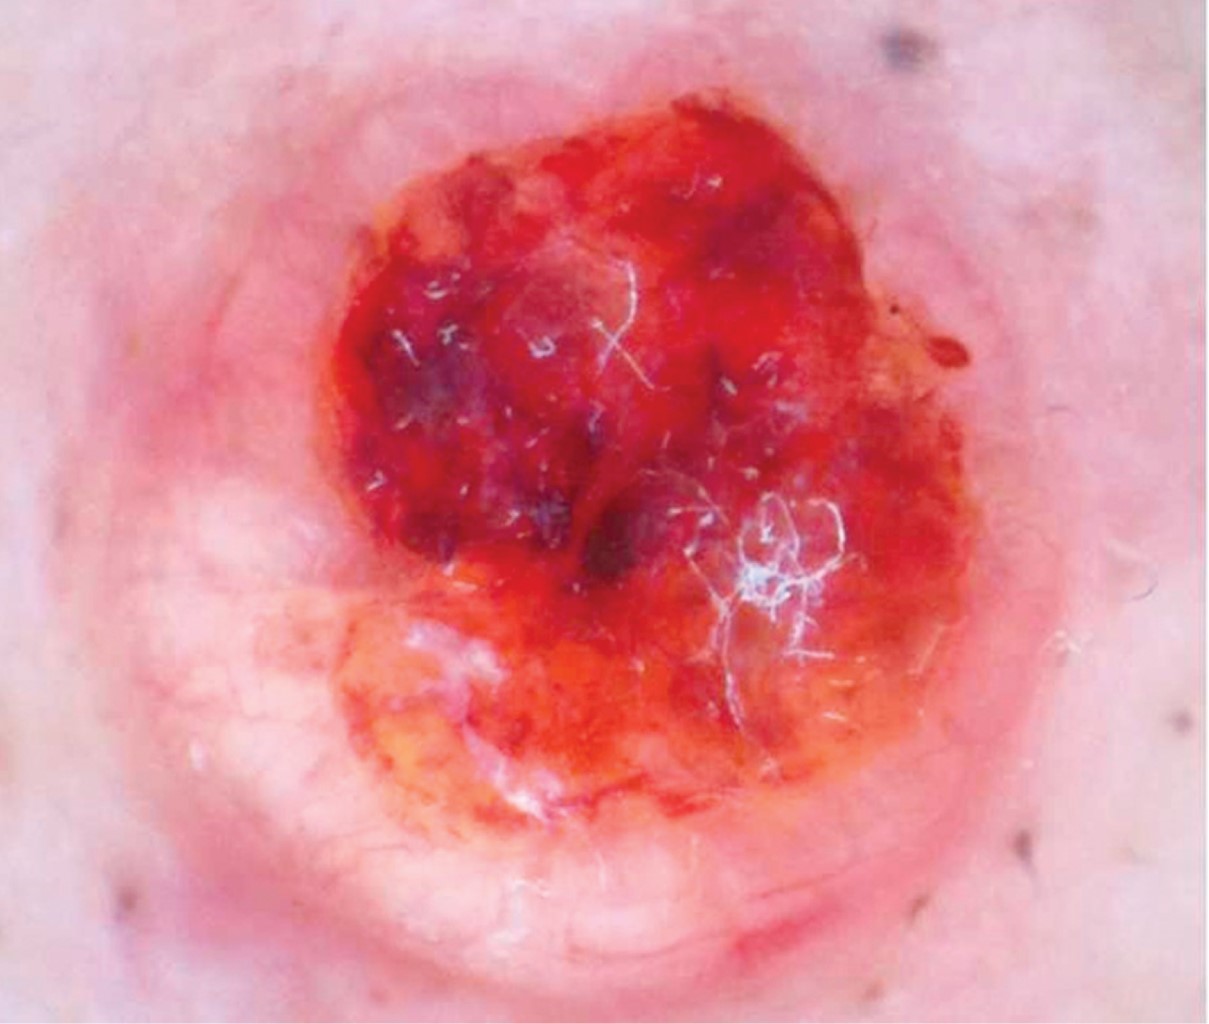

Mujer de 76 años con dermatosis localizada a la punta nasal, constituida por una neoformación hemiesférica, bien circunscrita, de 9 mm de diámetro, de superficie eritematosa, ulcerada, con bordes del color de la piel y telangiectasias (Figura 4). A la dermatoscopía se observan áreas rojo-vinosas mal definidas que alternan con áreas amarillentas sin estructura característica, costra y ulceración en el centro y vasos arborescentes en la periferia (Figura 5). Un año de evolución, con crecimiento en los últimos tres meses, con leve prurito y sangrado ocasional.

En la dermatoscopía se observan áreas ovoides amarillo-rosadas que corresponden a conglomerados de células con diferenciación sebácea, así como estructuras vasculares similares a los vasos arborescentes del carcinoma basocelular, e incluso áreas de ulceración.15,16